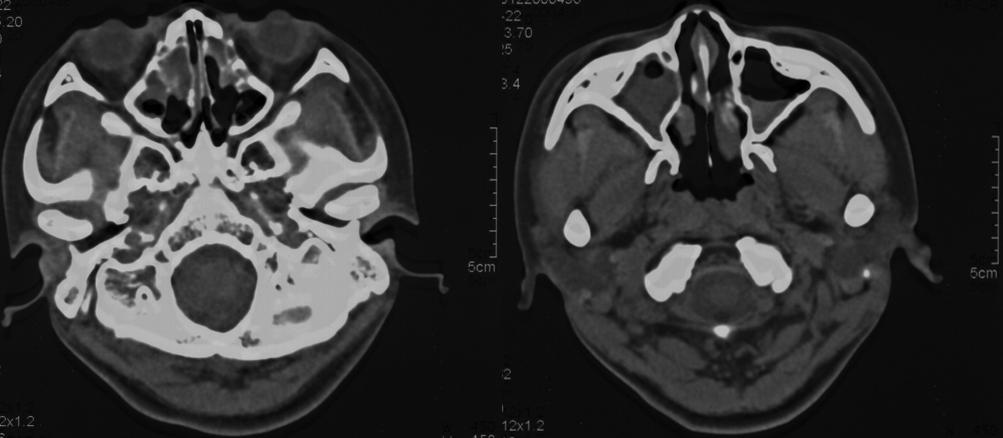

鼻窦CT(图2):双侧慢性上颌窦炎、双侧筛窦炎。

图2.2021年12月鼻窦CT

3、辅助检查:①实验室检查:WBC、N%轻度升高,CRP、真菌D-葡聚糖、内毒素试验阴性;②抗酸染色和T-SPOT阴性;③胸部CT:支气管扩张合并感染,可见「树芽征」,左下肺可见粟粒样结节;鼻窦CT:双侧筛窦、上颌窦可见黏膜增厚、水肿,未见骨质破坏,右侧筛窦较左侧病变重;④支气管镜活检组织电镜:部分上皮细胞纤毛少,有纤毛缺失、短小,未见动力臂(放大1000倍)。

3、辅助检查:①胸部CT:支气管扩张合并感染,有典型的「树芽征」,并且在左下肺可见粟粒样结节;②鼻窦CT:双侧筛窦、上颌窦可见黏膜增厚、水肿,未见骨质破坏,右侧筛窦较左侧病变重;③支气管镜活检物电镜:部分上皮细胞纤毛少,有纤毛缺失、短小,未见动力臂(放大1000倍);④全外基因检测:CCNO基因c.303C>A杂合变异以及c.248_252dup杂合变异,根据ACMG致病性证据,该变异为无功能(LOF)变异,可能导致翻译产生的蛋白截断或降解。